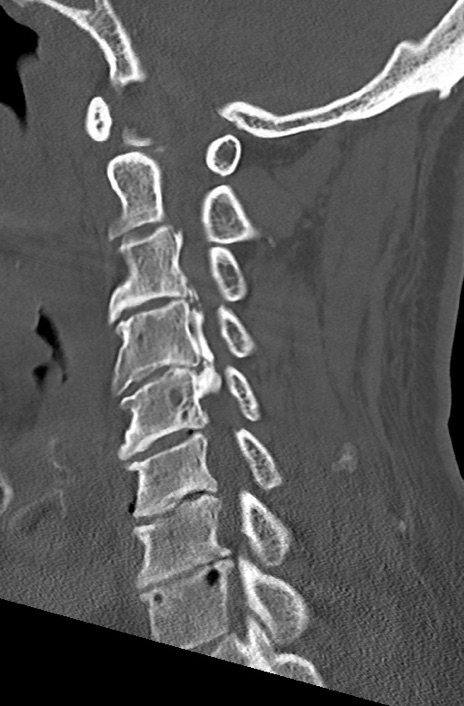

【整形】TIPS症例7 頚椎CT(矢状断像)

頚椎CT

矢状断像と横断像